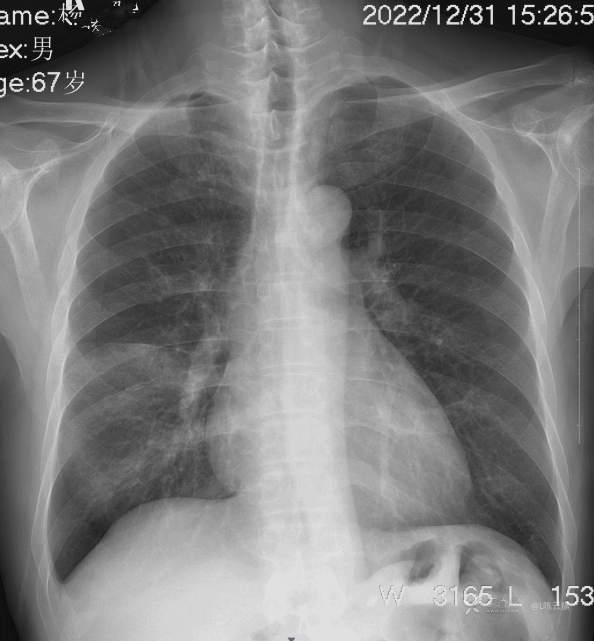

1、男67岁,精神病长期住院患者,发烧,伴咳嗽气紧两天。

2、又是胸片典型病例,你能正确描述和准确诊断吗?